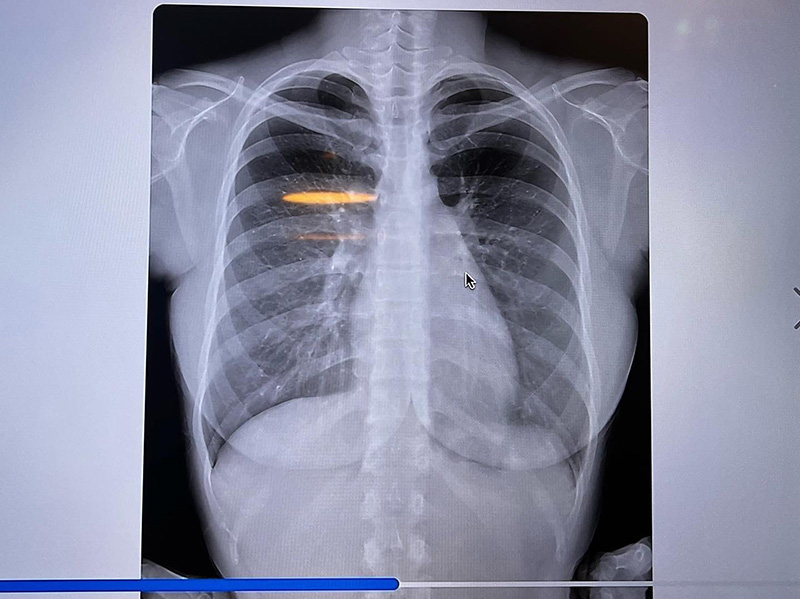

ด้วยกระแสลือหนักเข้า ทำให้ในที่สุดสาวฟูมินะ ซูซูกิ ตัดสินใจ ออกมาเปิดภาพเอกซเรย์ทรวงอกให้เห็นกันแบบเต็ม ๆ ตา จะได้รู้กันไปเสียที ว่าใหญ่ ๆ ที่เห็นอยู่นี้ คือขอแท้แม่ให้มา ธรรมชาติล้วน ๆ โดยมีการโพสต์ภาพลงในโซเชียลมีเดียต่าง ๆ ของเธอทั้งอินสตาแกรมและทวิตเตอร์ เมื่อวันที่ 14 กันยายน 2565 พร้อมแคปชั่นว่า

"รูปเอกซเรย์เต้าของฉัน ! 555 นี่พิสูจน์ได้หรือยังว่าหน้าอกของฉันคือธรรมชาติ ? ครั้งแรกเลยนะเนี่ยที่ฉันออกมาโชว์กระดูกกับไขมันให้ผู้คนได้เห็น"

ก็บอกได้เลยว่าลงทุนเอกซเรย์ให้เห็นกันเต็มตาขนาดนี้ หลาย ๆ คนก็คงจะหายคาใจกันเสียที ว่าความงามของเธอคนนี้ธรรมชาติหรือไม่